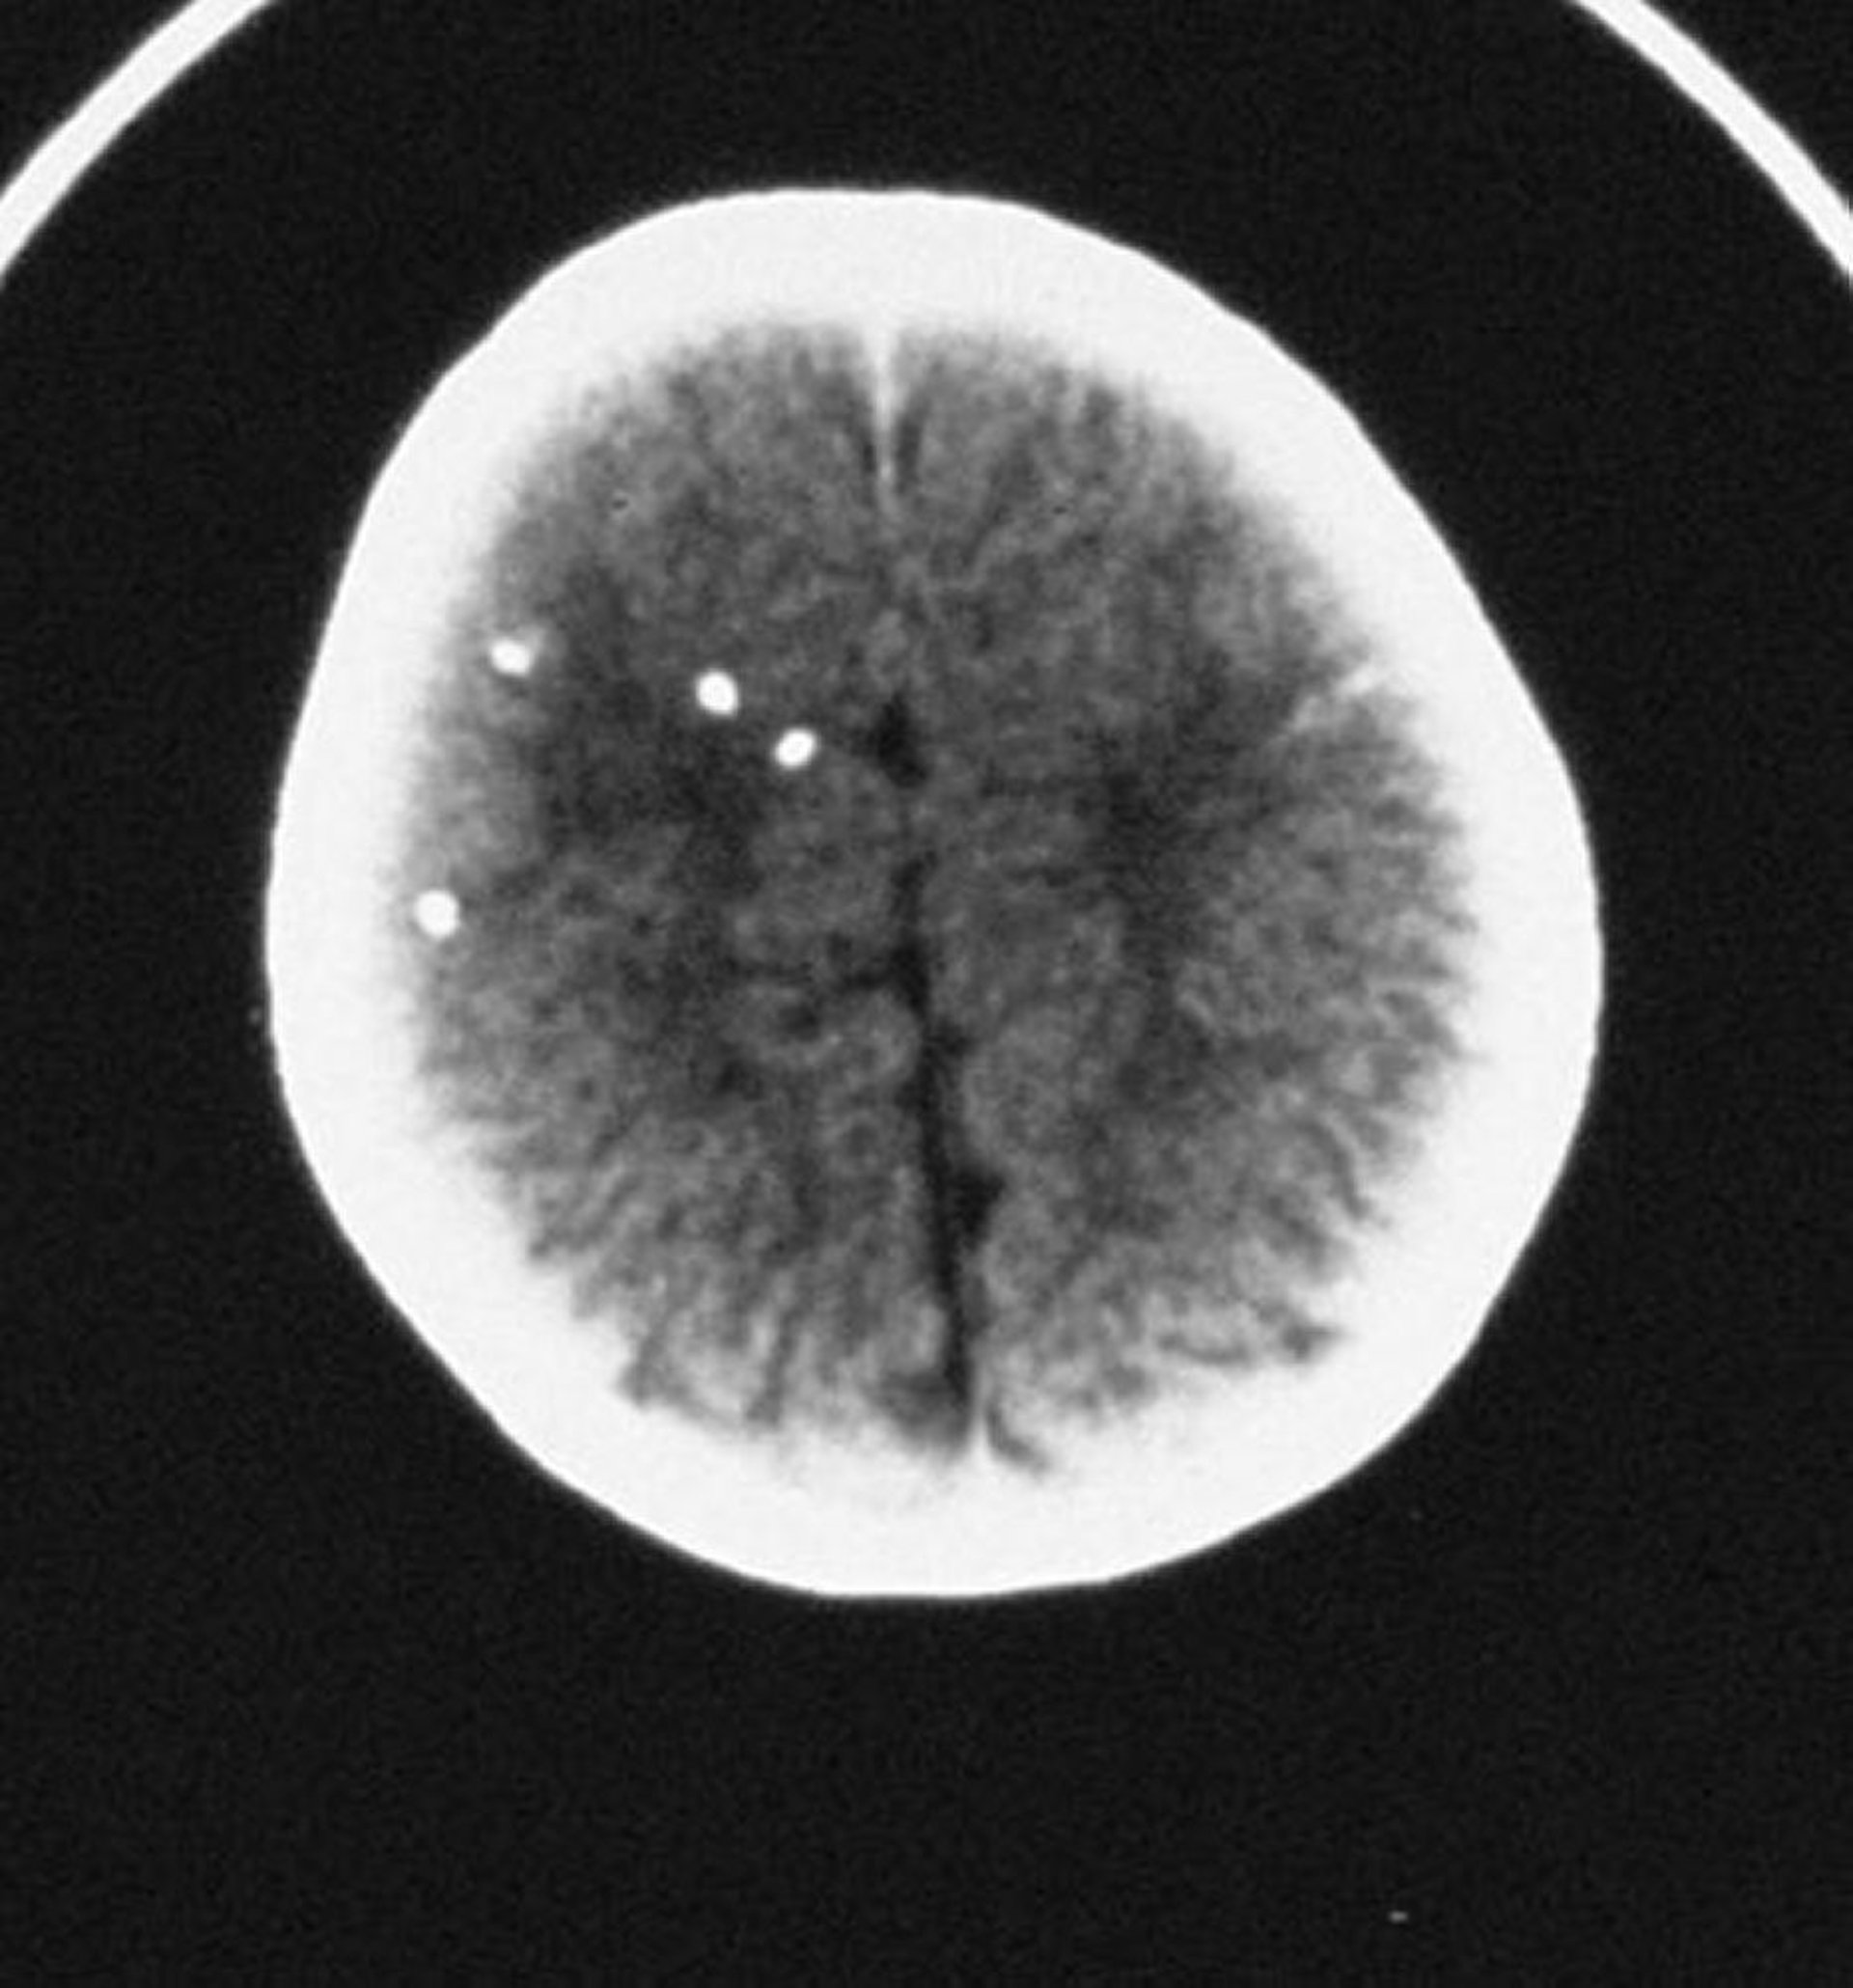

Neurologic involvement, often prominent, includes chorioretinitis, hydrocephalus, intracranial calcifications, microcephaly, and seizures. The classic triad of findings consists of chorioretinitis, hydrocephalus, and intracranial calcifications. Neurologic and ophthalmologic sequelae may be delayed for years or decades.

For infants with suspected congenital toxoplasmosis, serologic tests, MRI or CT imaging of the brain, CSF analysis, complete blood count, liver enzymes, brain stem auditory evoked responses, and a thorough eye examination by an ophthalmologist should be performed. CSF abnormalities include xanthochromia, hypoglycorrhachia, eosinophilia, pleocytosis, and increased protein concentration. The placenta is inspected for characteristic signs of T. gondii infection (eg, placentitis). Additional laboratory findings include anemia, thrombocytopenia, lymphocytosis, monocytosis, eosinophilia, and elevated transaminases. PCR testing of body fluids, including CSF, or tissues (placenta) can also be performed to confirm infection.

• Many organs may be affected, including heart, liver, lungs, and central nervous system; the classic triad of findings consists of chorioretinitis, hydrocephalus, and intracranial calcifications.

• Perform MRI or CT of the brain for all suspect cases.